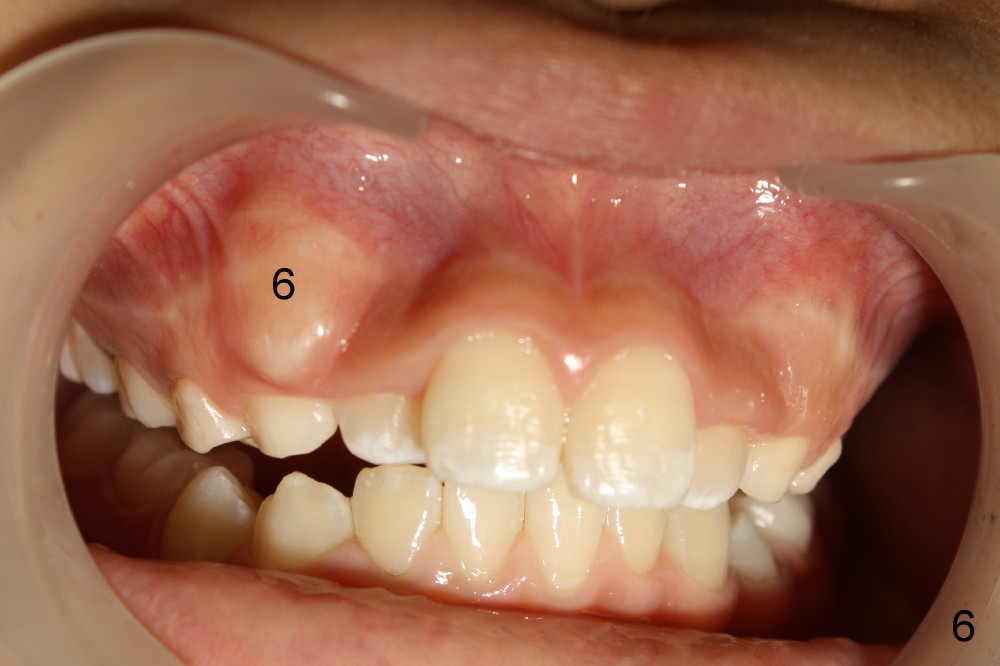

Eight-year-four-month-old boy shows early signs of Class II Division I malocclusion (Fig.2-5).  Panoramic X-ray was taken when he was 5 years 10 months old (Fig.1).

-Watch the erupting #6 on a future panorex compared to this one.

I am afraid that you have seen this patient (Koen) and his mom.  Anyway, he is 10 years 9 months now.  The teeth #6 and 11 appear to be erupting prematurely (prior to #5, and 12) and labially.  I have observed several of this type of cases.  It is apparent that premaxillary protrusion facilitates premature eruption of the upper canines, since there is premature formation of space for them to erupt.  What is your treatment plan or future one?  Thanks.